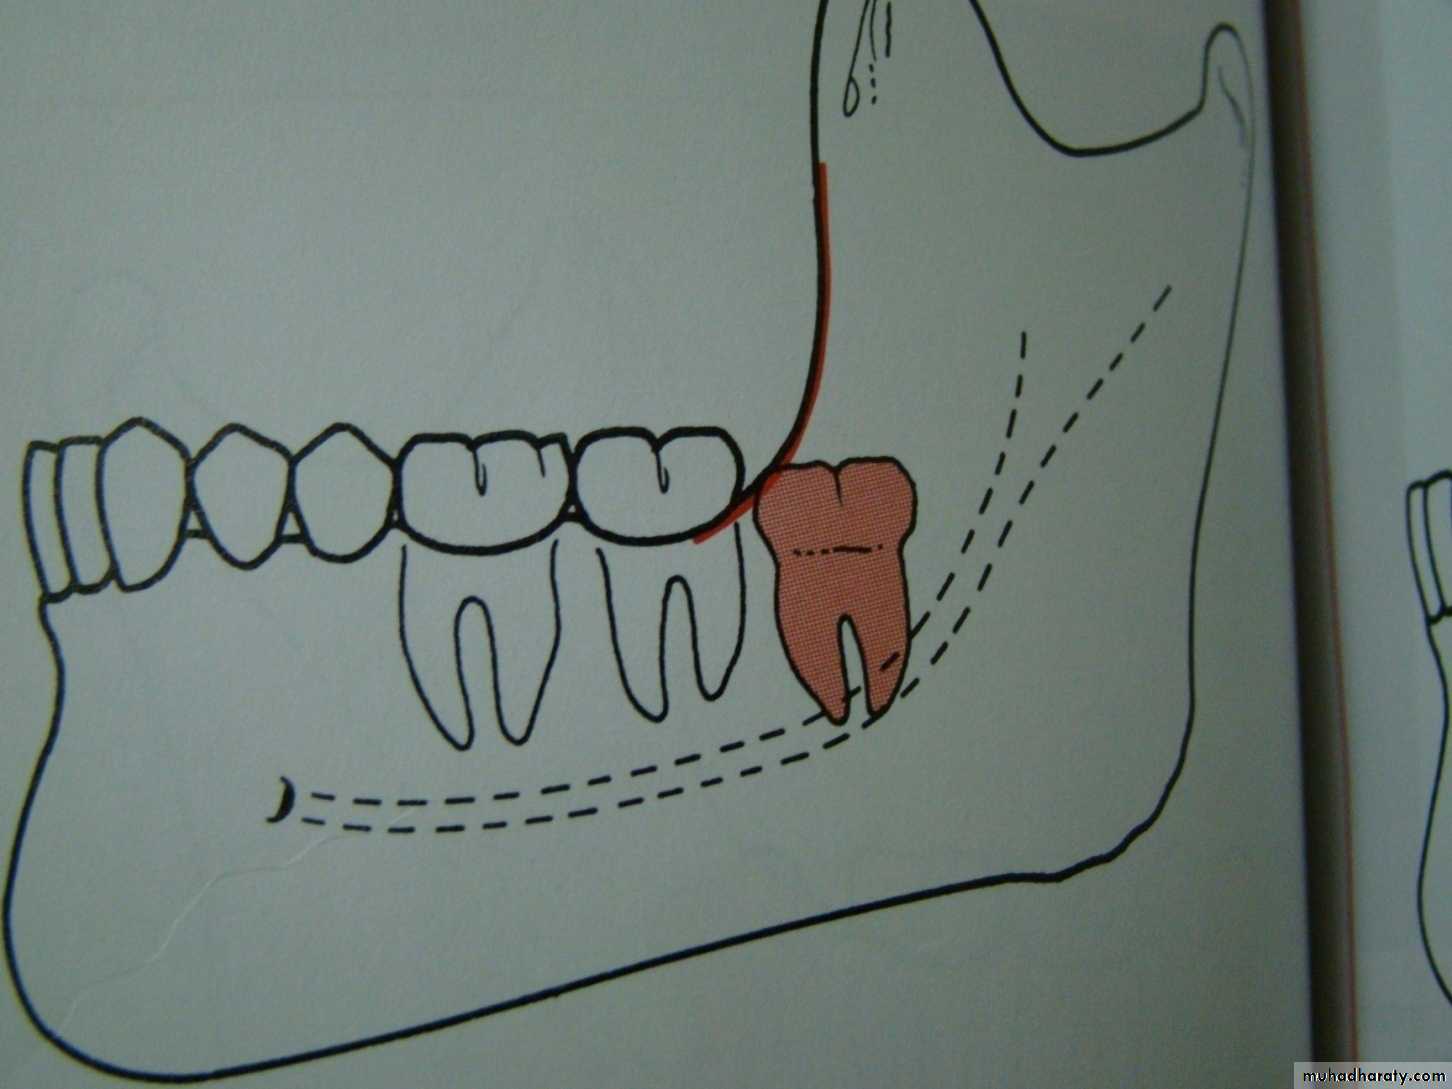

Winters classification of impacted lower third molar

mesioangular

hotizontalvertical

distoangular

Winter’s lines

1-White line: it is an imaginary line draw along the occlusal surface of erupted first and second molars extend posteriorly over 3rd molar region . Its benefit is to determine the angulations of an impacted tooth and its relationship with occlusal surface of erupted 2nd molar(depth).2- Amber line: It is a line drawn from the surface of bone laying distally to the 8 and to the crest of interdental septum or alveolar septum between 6 and 7. it determine the amount of bone removal

3-Red line : it is draw perpendicular from amber line to an imaginary point of elevator application located mesially to the CEJ except in Disto angular impaction it is distally located . It is used to measure the depth of the impacted tooth.

Note: Any tooth with red line length more than (5 mm) it is better to remove it under G.A.